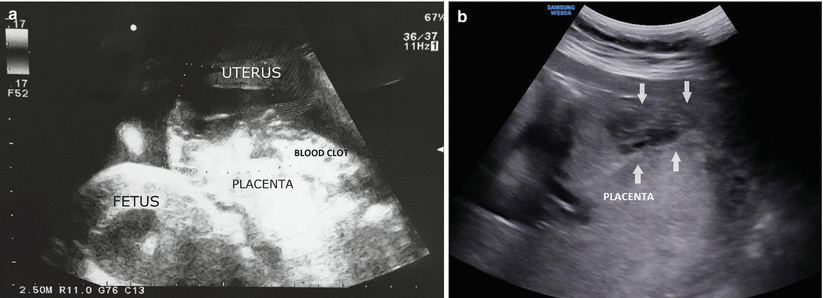

Fig. 3.1

Partial placental abruption